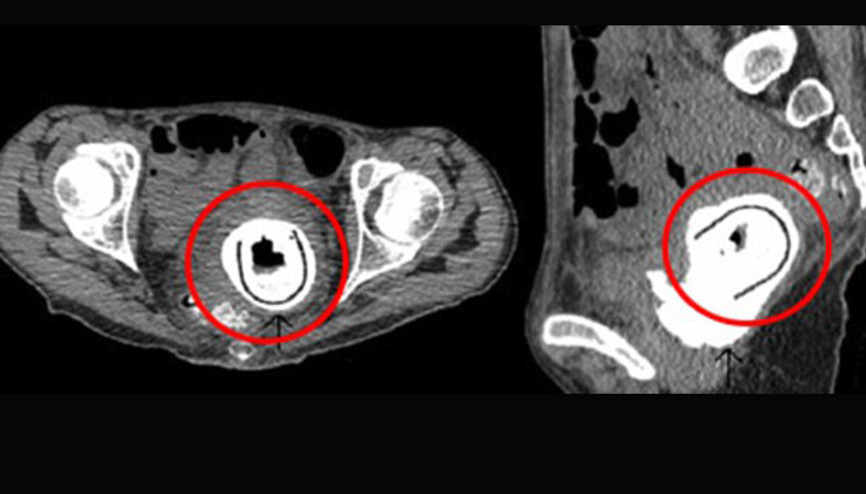

#Hamamİngiltere’de aşırı kilo kaybı ve halsizlik şikayetiyle hastaneye giden 38 yaşındaki bir kadının vajinasından idrar kesesine doğru çıkan yabancı cisim doktorları şaşkına çevirdi. Yapılan ameliyat sonrası kadının vajinasından yaklaşık 11 santimerelik bir seks oyuncağı çıkarıldı.